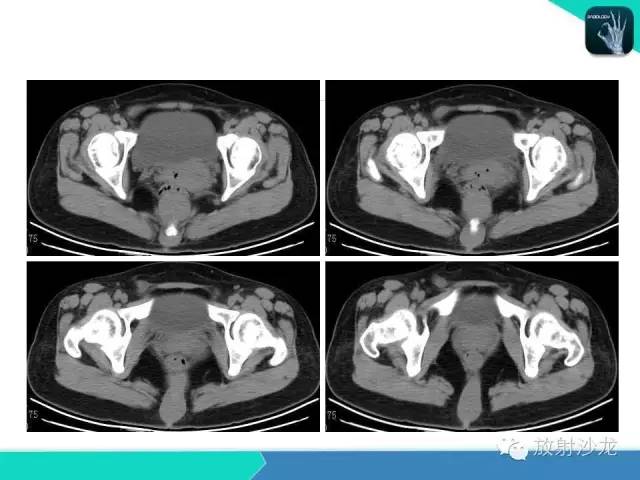

【病例】骶尾部表皮样囊肿1例CT